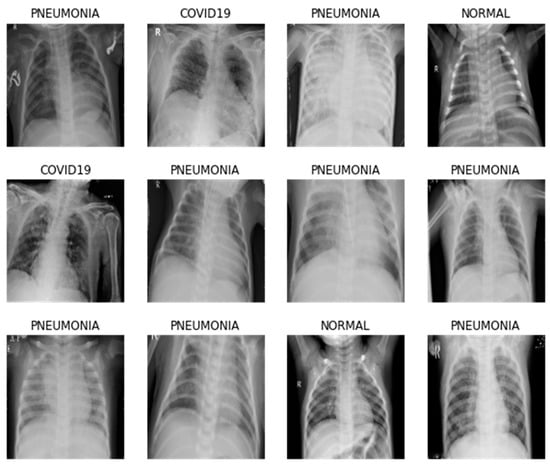

3.1. Data Acquisition